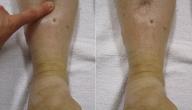

- الوذمة، تظهر الوذمة أو التورم عند مرضى زلال البول في عدة أماكن في الجسم منها: البطن، والوجه، ومحيط العينين، والذراعين، واليدين، والساقين.